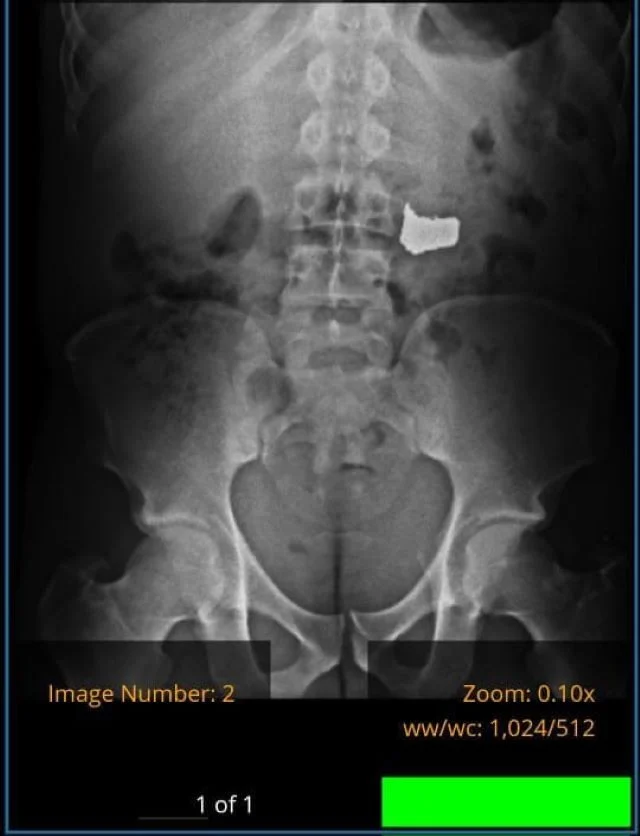

O assaltante foi conduzido para uma unidade de saúde e, após constatação através de Raio X, acabou apresentado na Central de Flagrantes.

De imediato, as guarnições da 11a CIPM encaminharam o suspeito para a UPA dos Barris. Os médicos realizaram um exame de Raio X e atestaram a presença da corrente.